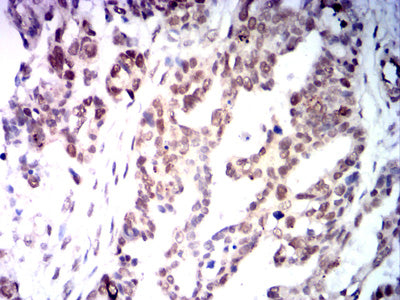

Immunohistochemical analysis of paraffin-embedded human Colon cancer tissues using MLH1 mouse mAb with DAB staining.

Immunohistochemical analysis of paraffin-embedded human Ovarian cancer tissues using MLH1 mouse mAb with DAB staining.